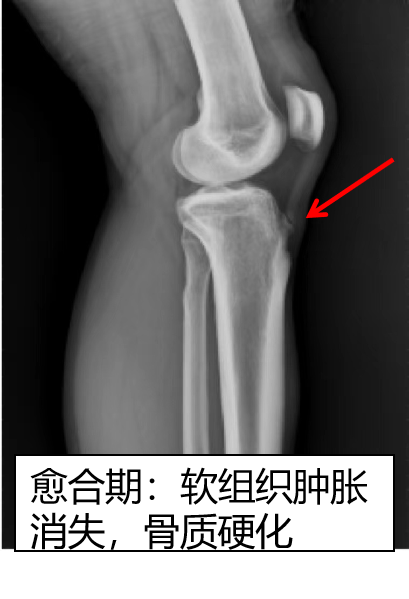

早期,仅表现为胫骨结节处软组织肿胀,密度增高。进展期,可见部分胫骨结节软骨撕脱,或出现游离骨碎片。愈合期,可见胫骨结节骨性愈合或游离骨块硬化,软组织水肿吸收。